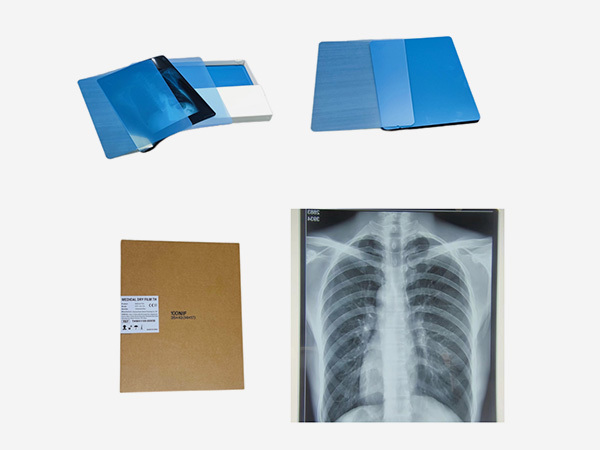

Independently develops and produces thermal film, medical laser film, and medical printing Film and other products.

As an indispensable and important tool in the medical diagnosis process, medical film plays a crucial role in disease detection, diagnosis, and treatment tracking.

Common types include X-ray films, CT films, and MRI films. X-ray films are used for general radiography, while CT and MRI films display detailed cross-sectional images of the body, aiding in accurate diagnosis and treatment planning.

The shelf life of medical films typically ranges from 1 to 3 years, depending on the type. Films should be stored in a cool, dry place away from direct sunlight, radiation, and magnetic fields. Maintain a temperature between 10 - 20°C and humidity around 40 - 60% to ensure optimal quality.

Ensure proper handling during film development, storage, and display. Use calibrated equipment for exposure and processing. For digital films, regular software updates and equipment maintenance are crucial to maintain accurate image representation.